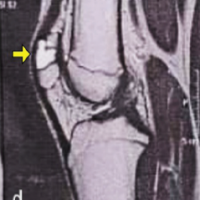

The patient was a 23-year-old right-hand dominant female preschool teacher who sustained a crush injury to the right hand and arm when she was riding in an ATV that rolled over. She was seen at a local trauma center and discharged in a splint. The patient presented to the clinic 3 weeks post-injury with complaints of numbness and tingling in the radial digits and diffuse swelling of the hand. Radiographs and a CT scan of the right hand were performed, which demonstrated right second and third CMC fracture dislocations, right fourth metacarpal base and capitate fractures, and a right displaced ulna shaft fracture (Fig. 1 and 2). There was also concern for acute carpal tunnel syndrome due to the numbness in the radial digits. Surgery was recommended for fixation of the second and third metacarpal fracture dislocations and capitate, as well as carpal tunnel release.

Figure 2: Pre-operative CT of the right hand in splint. (a, b, c, d, e) CT shows second and third carpometacarpal base fracture dislocations, fourth metacarpal base and capitate fractures, and displaced ulna shaft fracture.